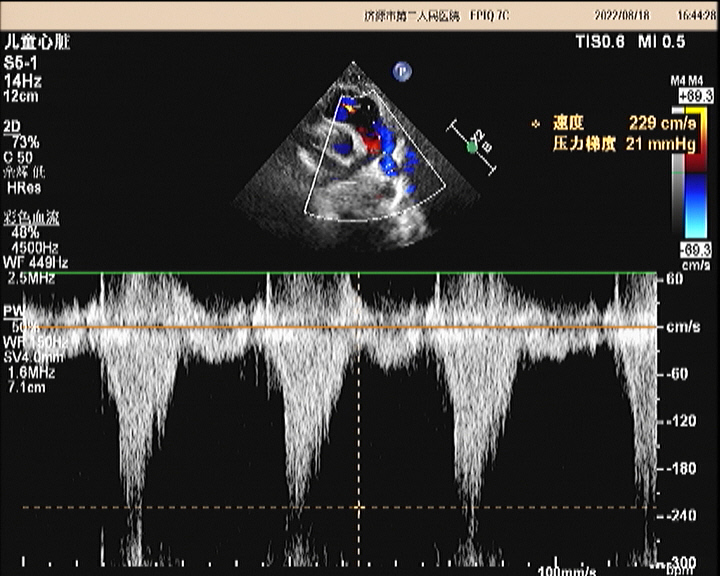

超声所见:各房室大小正常,肺动脉主干内径增宽,约20mm,左右肺动脉内径分别约10mm、8.7mm,左肺动脉起始于主肺动脉的右侧并向左侧走行,右肺动脉起始于主肺动脉左侧向右走行。主动脉内径正常,搏动好。各瓣膜回声正常,肺动脉瓣开启可,关闭欠佳,余瓣膜启闭自如。房室间隔连续完整,室壁厚度及运动收缩幅度正常。CDFI:主肺动脉及左、右肺动脉前向流速增快,主肺动脉峰值流速:2.5m/s、左肺动脉峰值流速:2.2m/s、右肺动脉峰值流速:1.7m/s;肺动脉瓣口探及舒张期少量返流。

超声提示:1.左右肺动脉交叉 2.肺动脉主干内径增宽 3.肺动脉主干及左、右肺动脉前向流速增快 4.肺动脉瓣少量返流

(左肺动脉峰值流速)